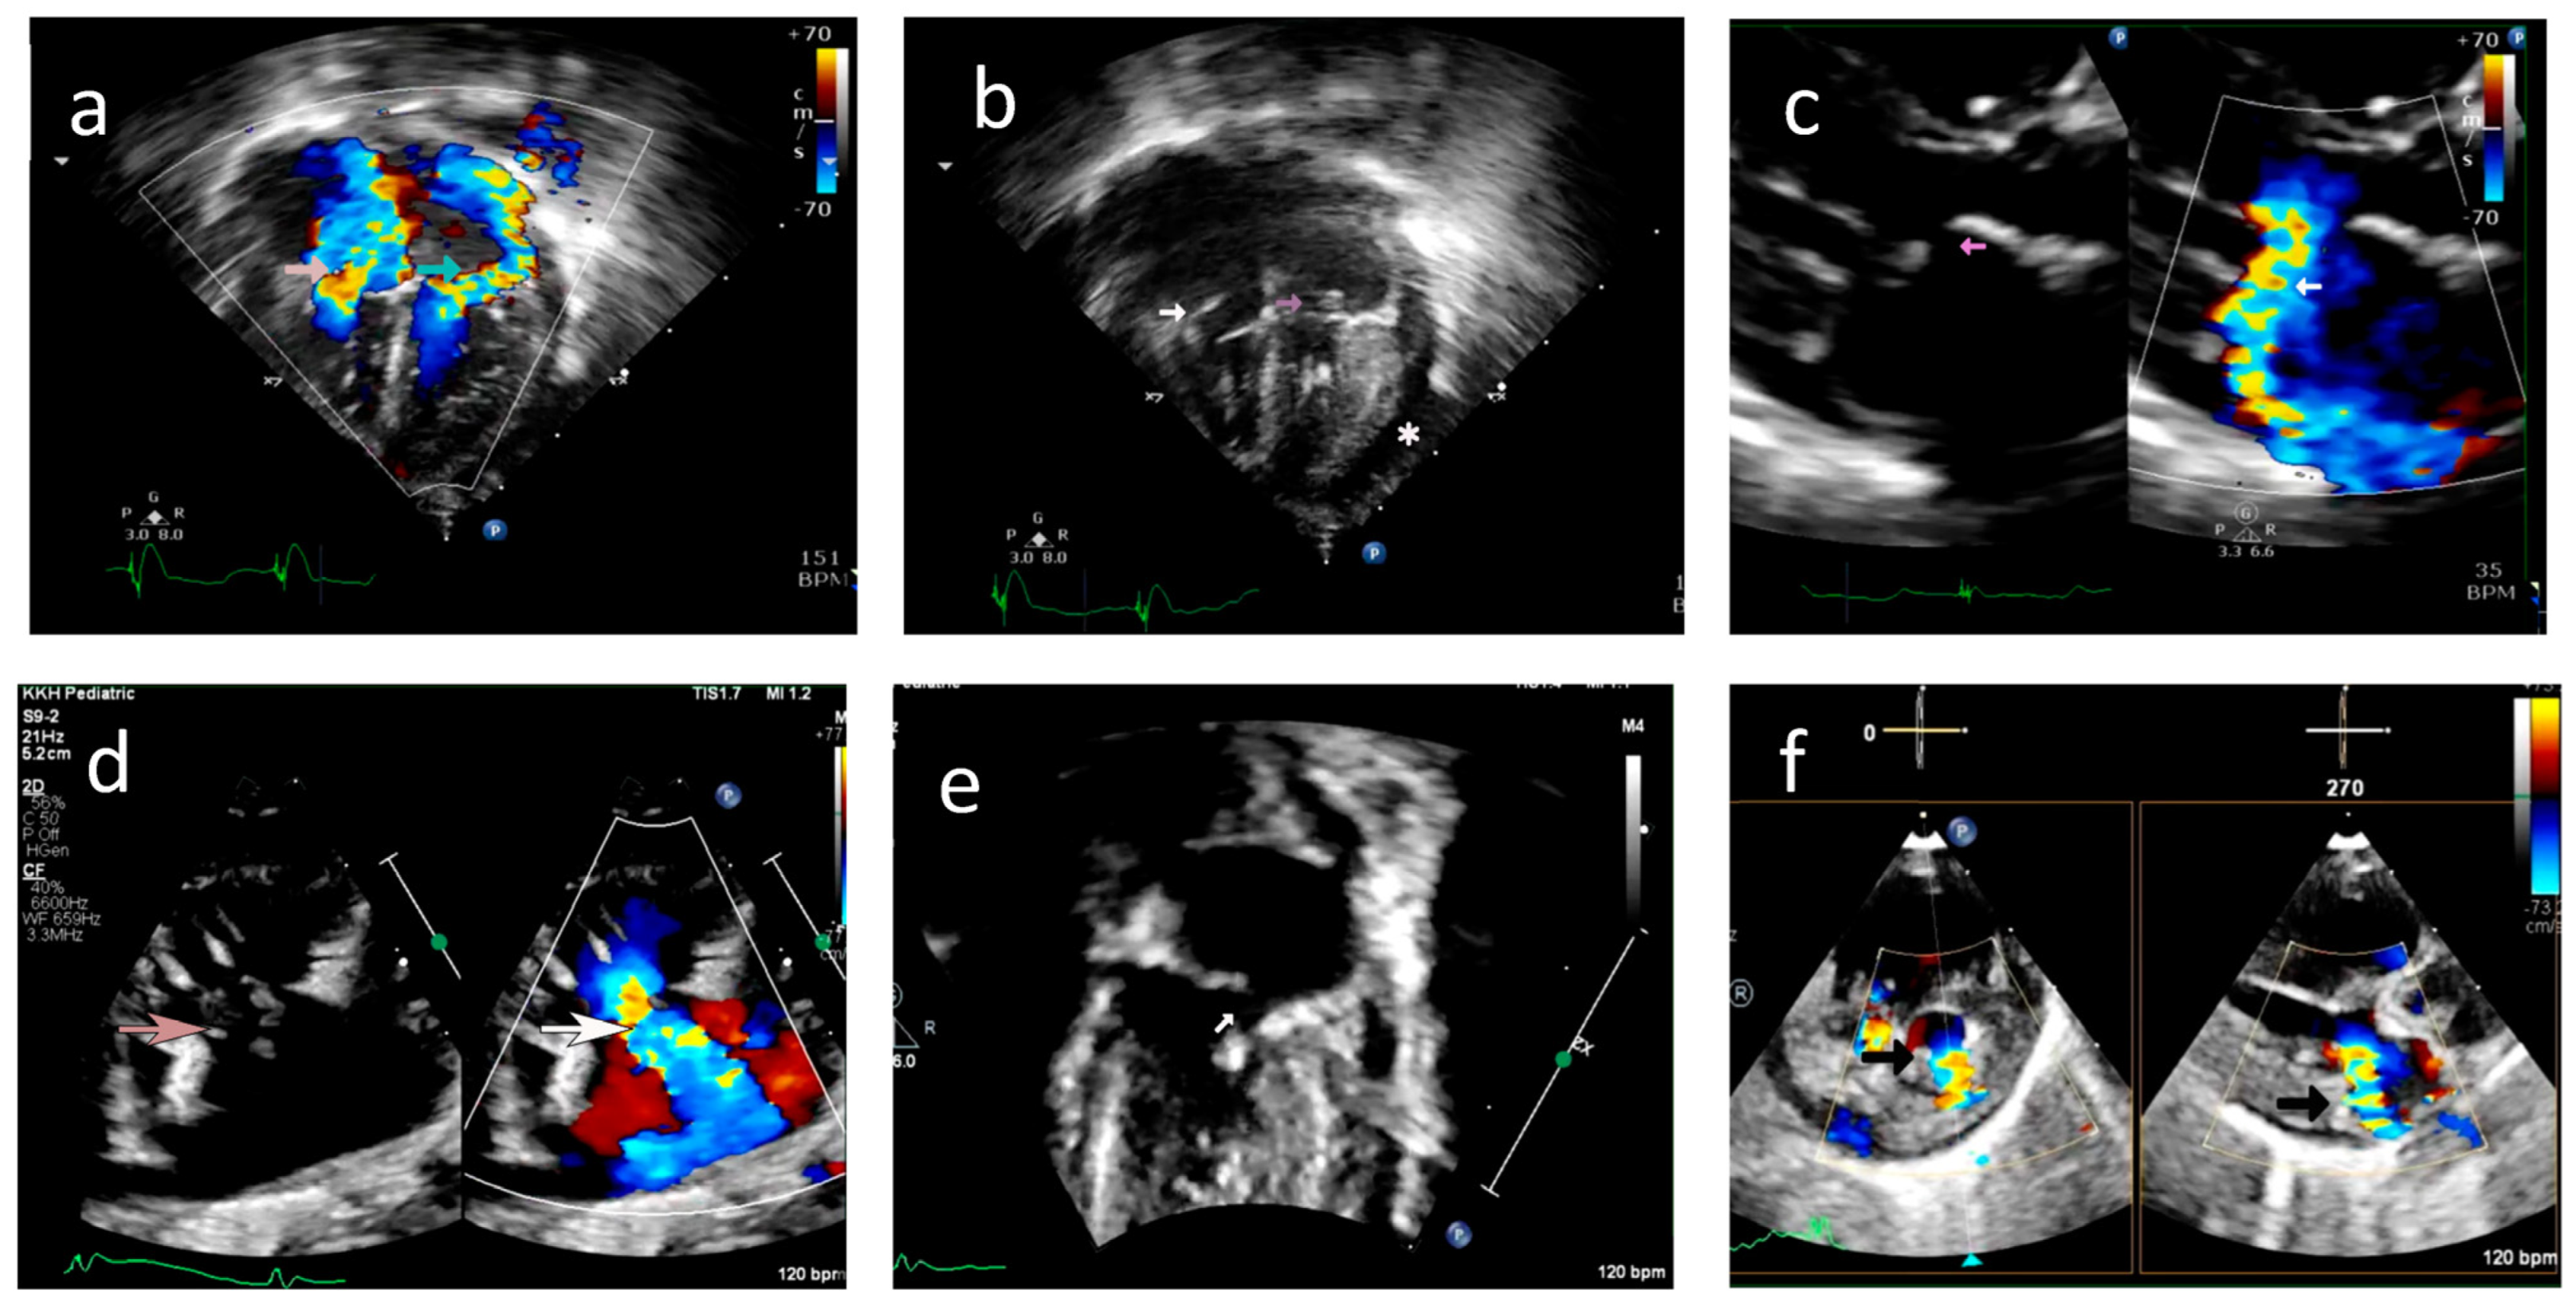

2.1.1. Case A

2.1.2. Case B

5.5. Echocardiography Correlation